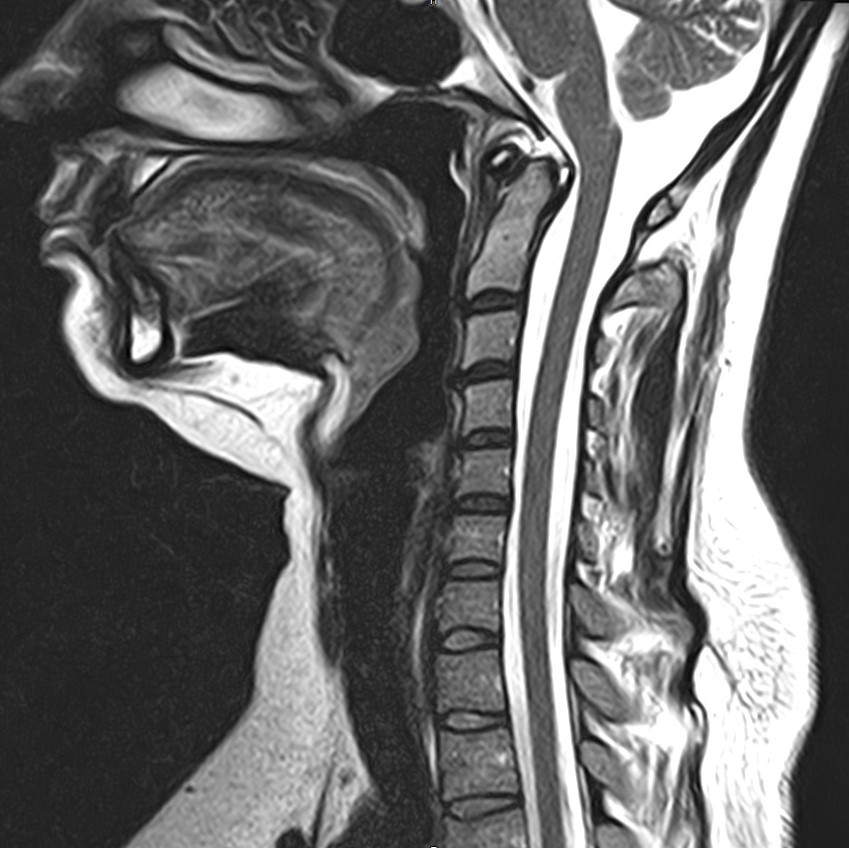

Для того, чтобы оценить состояние шейных позвонков с прилегающими тканями и одновременно визуализировать плечевой сустав, в нашей клинике выполняется комплексное обследование, включающее два протокола: МРТ шейного отдела позвоночника и МРТ плечевого сустава.

Метод МРТ позволяет оценить состояние всех анатомических областей шейного отдела позвоночника: костную структуру позвонков, спинной мозг с отходящими от него нервными корешками и окружающие мягкие ткани. Протокол обследования плечевого сустава включает оценку костной структуры, суставной капсулы, полости сустава с выстилающей его синовиальной оболочкой, связок, сухожилий, мышц и окружающих мягких тканей.

В клинике «Доступная медицина» исследование проводится на современном высокопольном томографе закрытого типа TOSHIBA VANTAGE TITAN 1,5 Тесла с превосходной  разрешающей способностью, которая обеспечивается высокой индукцией магнитного поля. Аппарат выполняет сканирование послойно в различных плоскостях и на основе этого создает 3D-изображения с высочайшей точностью и достоверностью, что позволяет эффективно ставить диагноз и назначать необходимое лечение.